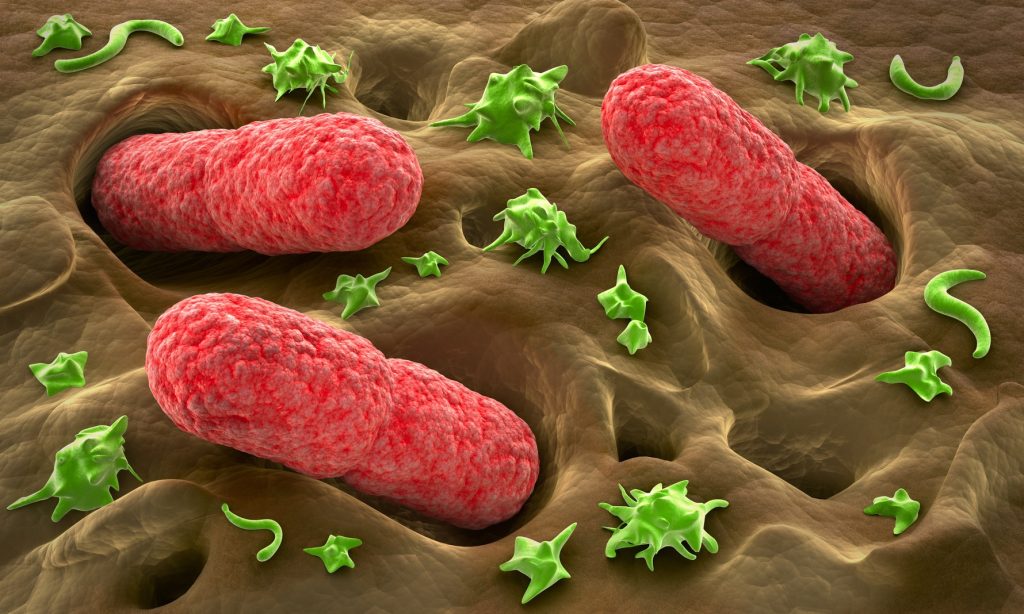

Καρκίνος